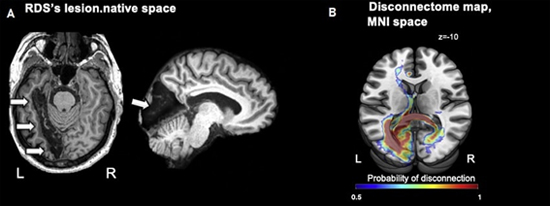

Avant son AVC, RDS percevait et nommait les couleurs normalement. Après son AVC, une IRM a révélé une lésion dans la région gauche de son cerveau. Cette lésion aurait apparemment coupé la mémoire des noms des couleurs de RDS, de sa perception visuelle des couleurs et de son système de langage. Cependant, RDS pouvait toujours regrouper la plupart des couleurs, même impossibles à nommer, dans des catégories telles que sombre ou clair ou comme un mélange d’autres couleurs.

(A) IRM montrant les lésions cérébrales post-AVC de RDS (flèches) et (B) Cartographie IRM des déconnexions cérébrales entre les deux hémisphères. Crédits : Katarzyna Siuda-Krzywicka et al. 2019